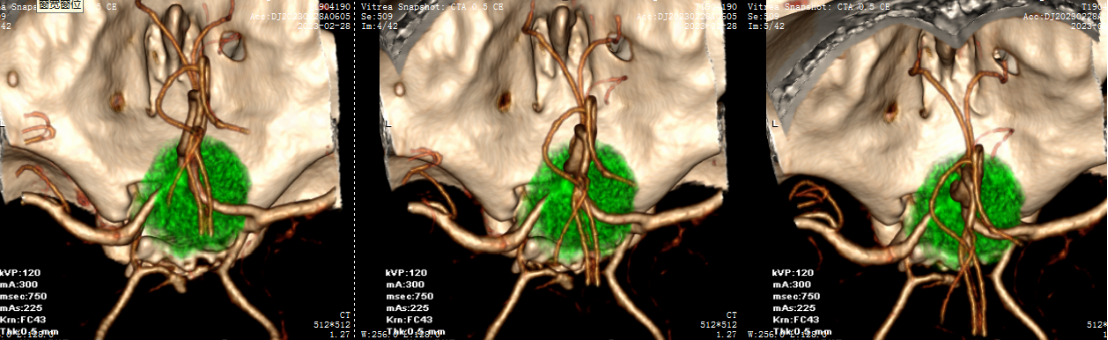

自近蝶窦前壁处向左侧推挤鼻中隔,离断筛骨垂直板,咬除部分近蝶窦处骨性鼻中隔,分离双侧鼻粘膜显露蝶窦前壁,自蝶窦开口上方做沿鼻中隔做粘膜瓣备用,末端到中鼻甲位置,将粘膜瓣压向下鼻道,高速磨钻磨除蝶窦下壁骨质,鞍结节骨质。术中视神经管清晰可见,给予保护,海绵间窦出血给予流体明胶+凝血酶止血;等离子刀一边止血一边切开硬脑膜见白色肿瘤质韧,边界清晰,大脑前动脉分支粘连于肿瘤表面,给予小心分离,以刮圈,咬切钳等小心清除肿瘤组织;内镜下将肿瘤完整切除;取右侧大腿皮下脂肪及阔筋膜备用,以人工硬膜修补和明胶海绵封闭鞍底硬膜,将脂肪放置于切口,并缝合于鞍底硬脑膜上固定铺平,阔筋膜覆盖于脂肪外边,蝶窦内充填明胶海绵止血,鼻粘膜瓣覆盖于蝶窦;碘仿纱条填塞鼻腔;护士清点棉条、器械、纱布无误,撤出鼻镜。

鞍结节脑膜瘤(tuberculumsellaemeningioma TSMs)仅占颅内脑膜瘤的4%~10%。鞍结节脑膜瘤沿脑膜向周围生长,向前可达眶尖,向后可达斜坡及小脑幕,向外沿中颅窝底扩展,向内可累及鞍内垂体腺。常最早侵犯视神经,多以视力障碍为首发症状,产生颅高压为引起头痛、恶心、呕吐,侵犯垂体会出现垂体功能障碍相应症状。